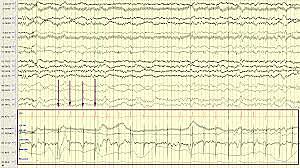

• EEK/EKG

EEK/EKG

A Dutch doctor and physiologist called Willem Einthoven invented the first practical electrocardiogram (ECG or EKG).